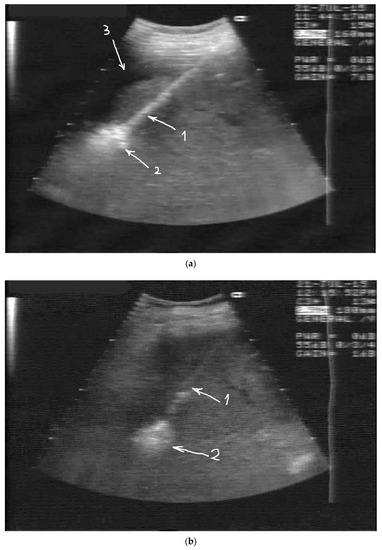

2. Case Presentation